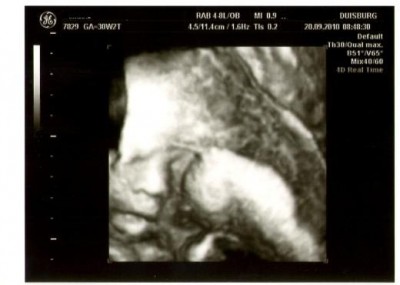

@me: Wir hatten heute morgen Mia-TV!

Mit Mausi ist alles gut, entwickelt sich richtig toll, alles zeitgerecht und CTG war auch super!

Mia wiegt jetzt 1800g und ist ca. 41 cm groß!

Der US war super schön und wir konnten sehen wie sie sich an der Nase gekratzt hat und am gähnen war!Das sah richtig süß aus! :lol:

Nur auf Fotos hatte sie keine Lust und hat sich in den Mutterkuchen eingekuschelt, so das man nur ein wenig sehen kann aber ich zeigs trotzdem!

Und in 2 Wochen ist wieder US! :juhu: